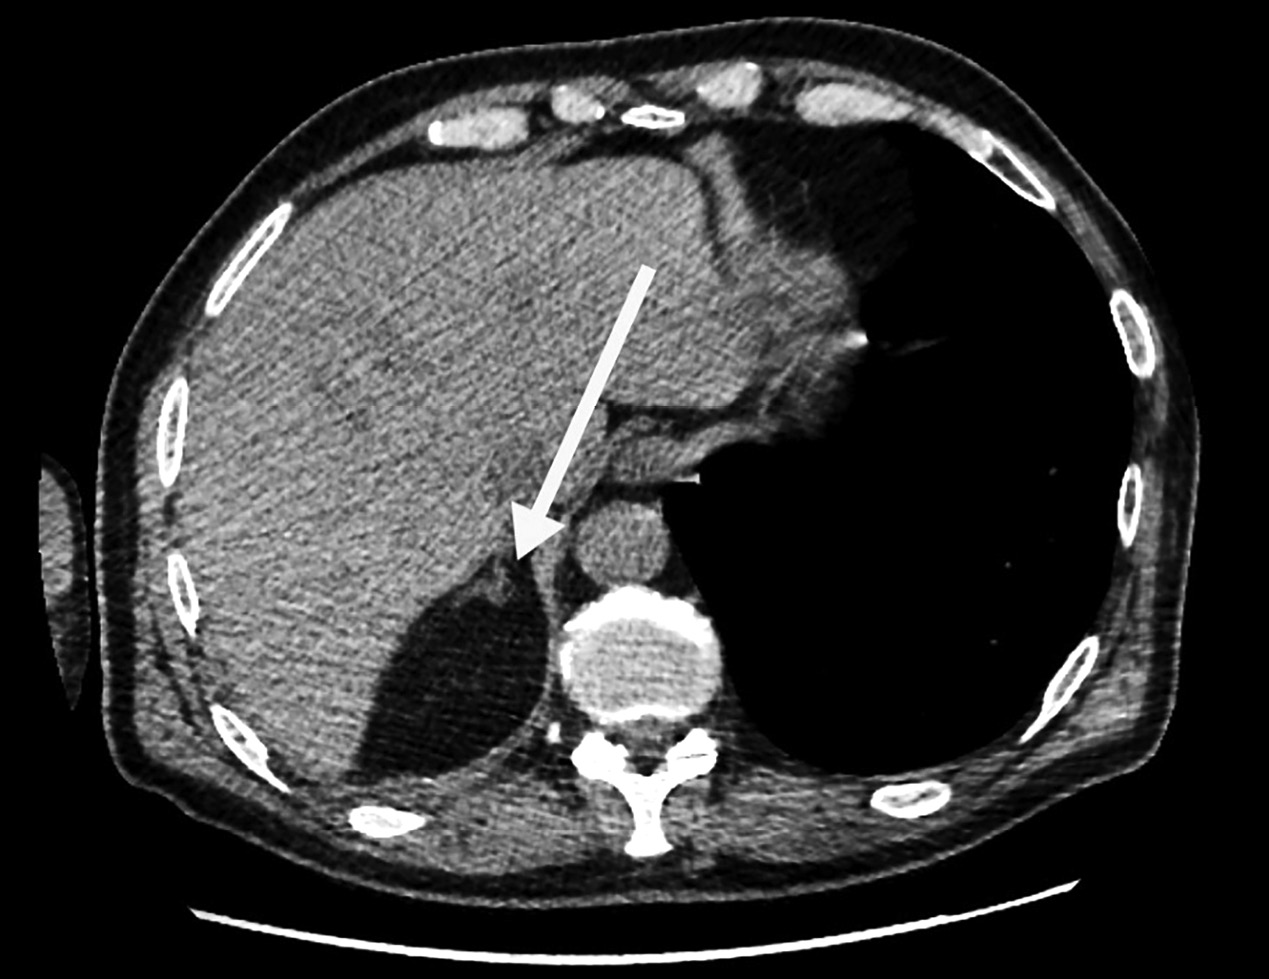

2. Рисунок 2. Контрольная МСКТ органов брюшной полости от 22.07.2022. Состояние после левосторонней адреналэктомии. Визуализируется правый надпочечник с объемным образованием. | |